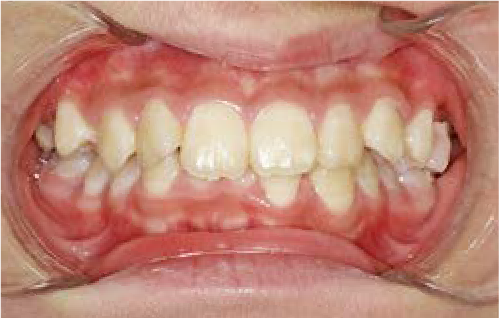

前歯のすき間や歯並びの乱れが見られ、普段の生活の中で、無意識に舌を押しつけるクセや飲み込み方のクセが確認されました。

治療を終えて

装置をしっかり使うことで、あごの位置が整い、舌の正しい位置や動きが戻り、ほっぺたやくちびるの筋肉の使い方も改善されました。その結果、歯並びが整いお口の機能も良くなりました。もちろん非抜歯での治療です。

主訴・治療内容 他院で抜歯のうえ、ブラケット矯正を勧められたが、できれば歯を抜かずに治療したいとの要望で来院されました。

治療期間 5年4ヶ月

費用 495,000円(税込)